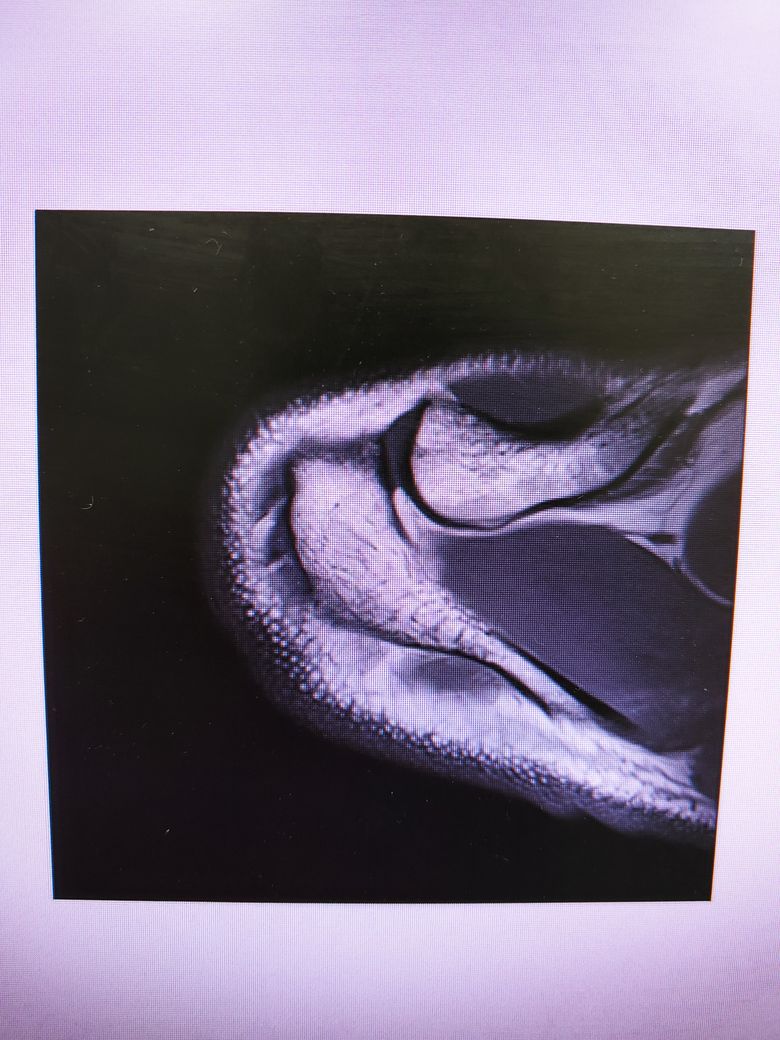

팔이 잡아당겨지는 사고 이후 통증이 지속되어

조영제 투입 후 mri 촬영을 하였습니다.

진단명은 상부관절와순파열(슬랩)이며

슬랩이 맞나요? 맞다면 파열 진행 정도는 어느정도인지..